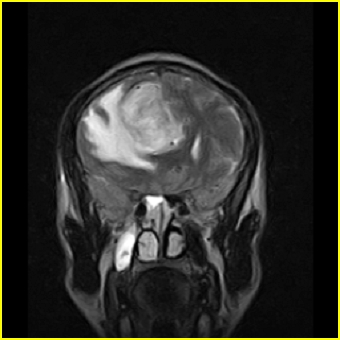

男,45岁,头部剧烈疼痛伴呕吐5天。

右侧额叶见较大的类圆形长t1信号环绕等t1环影,长t2信号环绕短等t2环,周围见明显水肿占位征,中线结构左移,男,45岁,头部剧烈疼痛伴呕吐5天。

病灶紧贴大脑镰,周围见有大片水肿,考虑:1.脑膜瘤伴水肿,2.胶质瘤。

右侧额叶,见一占位病灶,t1像病灶、水肿长t1;其间为短t1环行信号。t2像病灶、水肿长t2,其间为短t2环行信号。占位效应明显,中线左移,右测脑室受压闭塞。结合患者发病较急。首先考虑:右侧额叶脑脓肿形成。鉴别:1、转移瘤,多发多见2、胶质瘤。建议增强

t1加权肿瘤呈低信号,肿瘤壁呈等信号.t2 加权时肿瘤呈高信号,肿瘤壁呈等信号.

考虑1脑脓肿.2恶性胶质瘤.